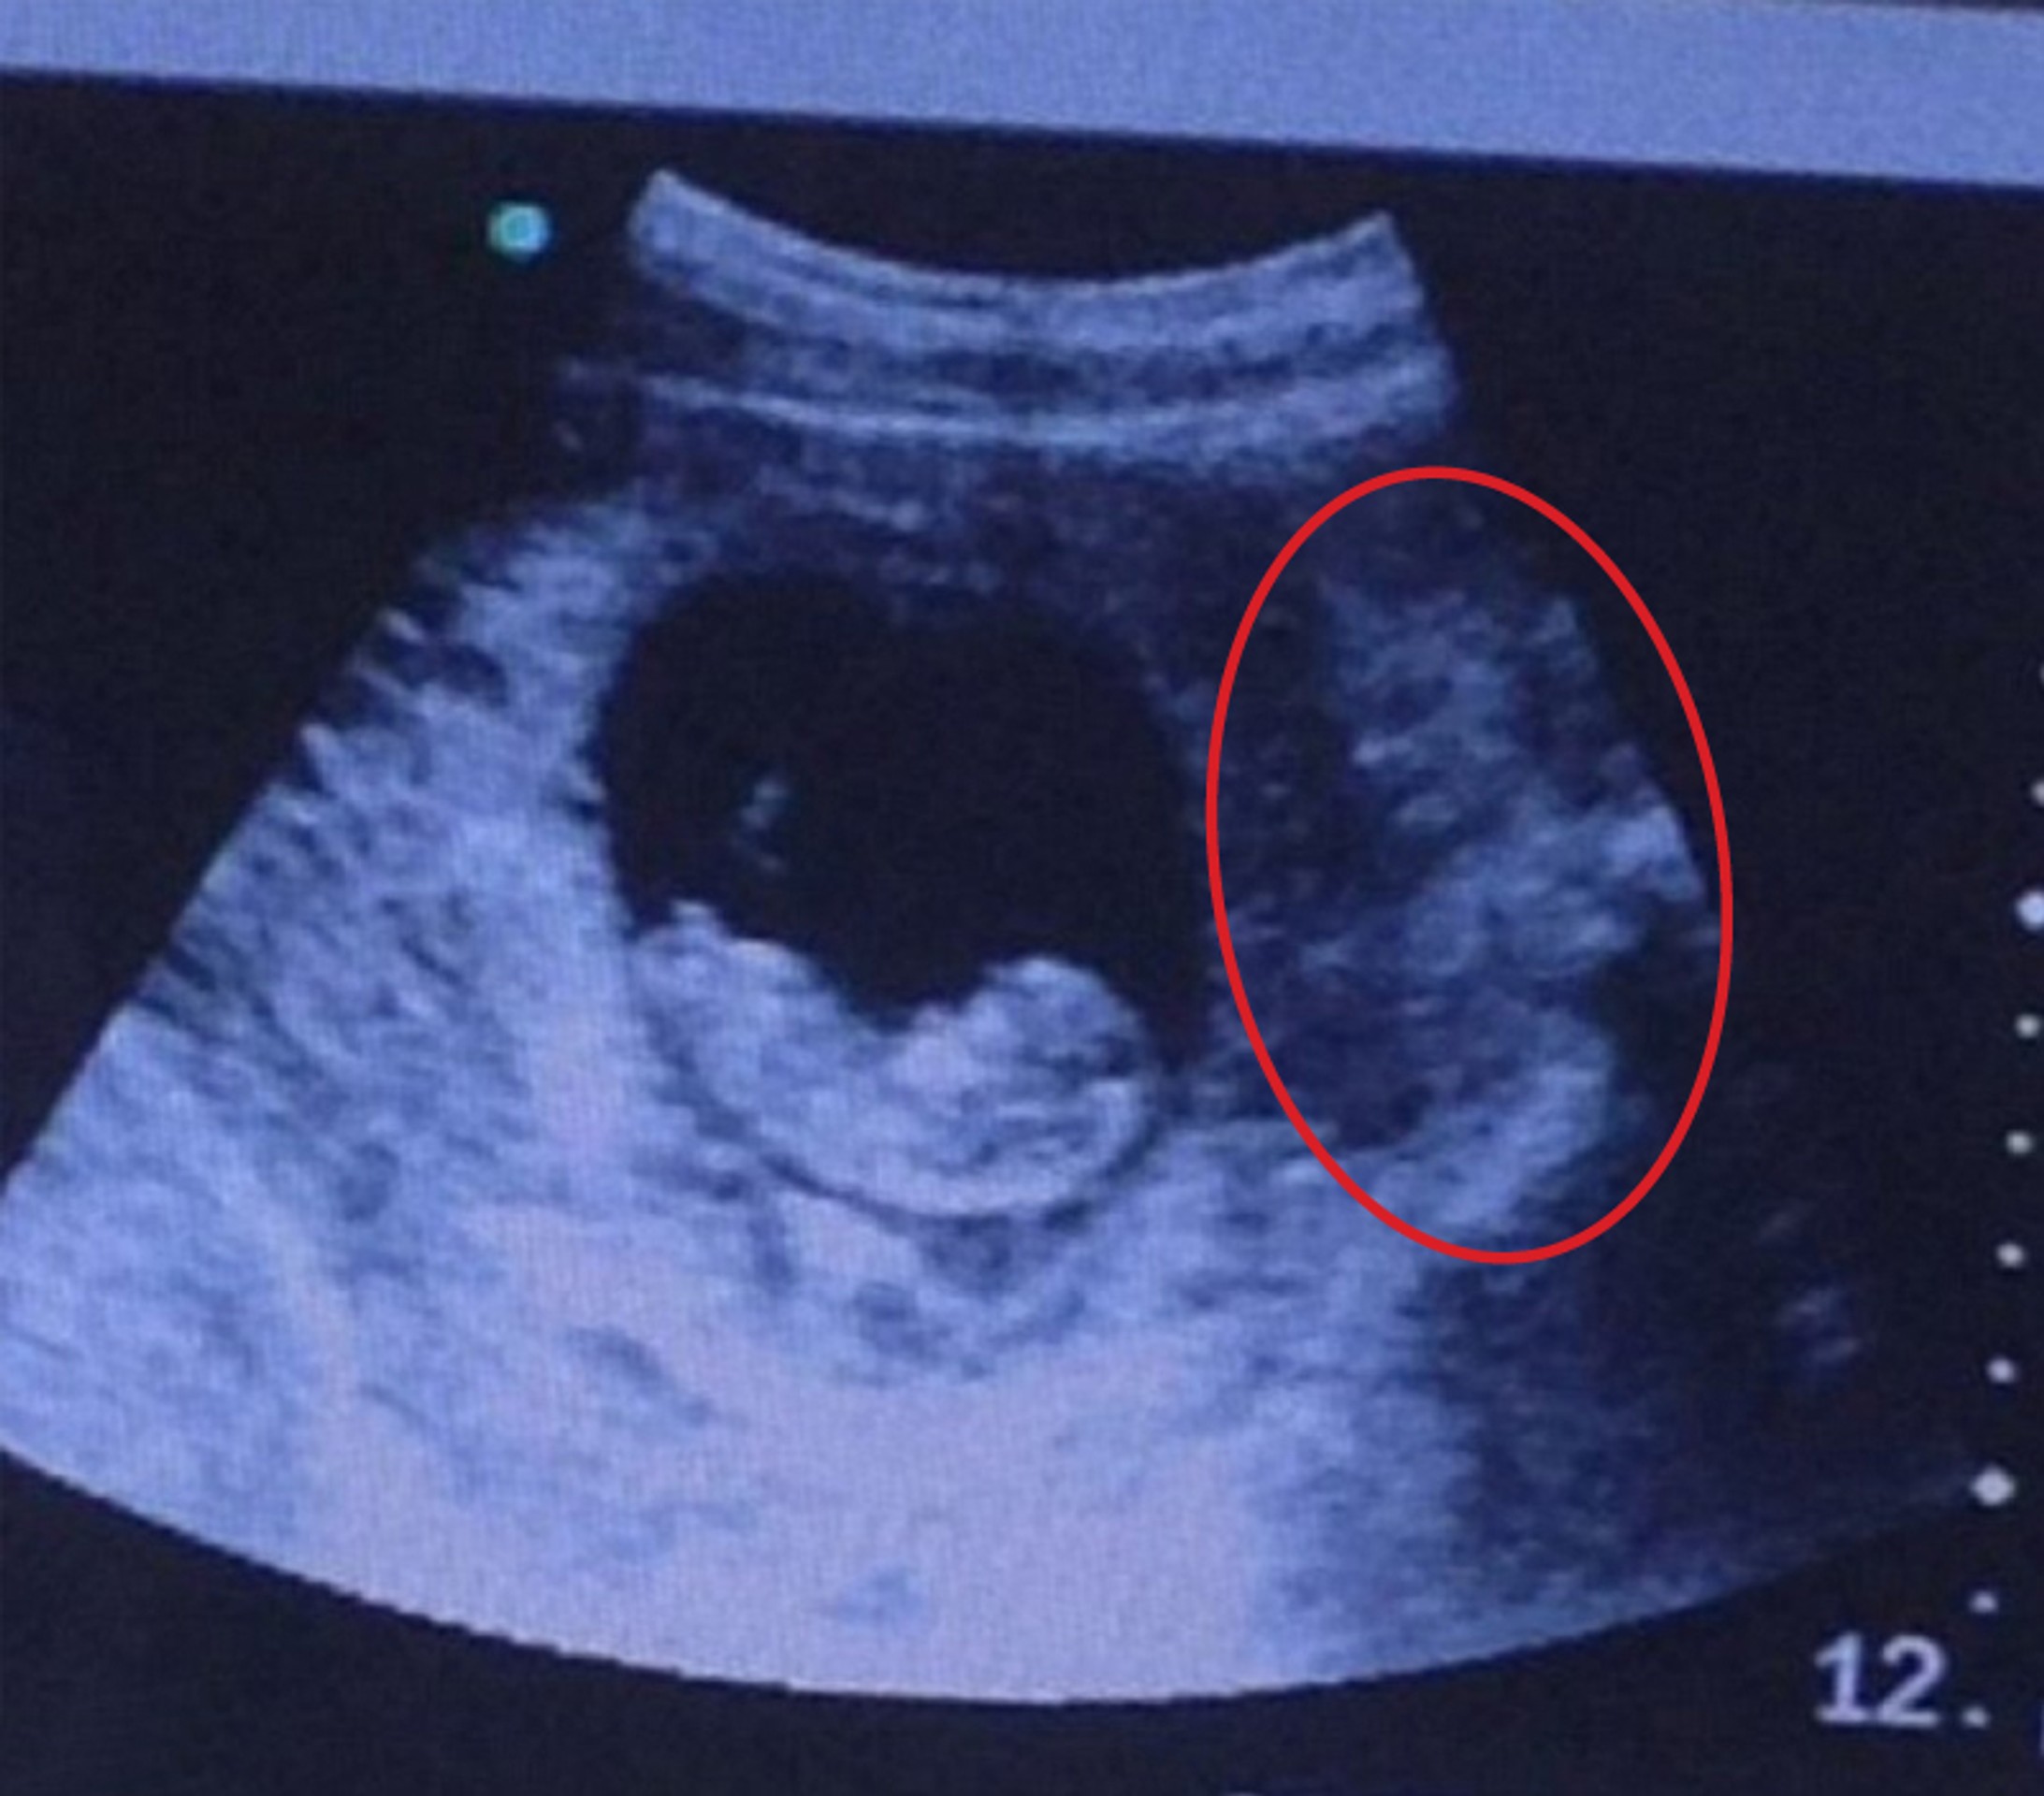

From dijasporainfo.net

ZA 20 GODINA RADA OVO NISAM VIDEO Nećete verovati šta je beba uradila u stomaku Mama Petrova Ultrazvuk Smještena u zagrebu, na adresi petrova ulica 13, klinika za ženske bolesti i porode u radu objedinjuje više područja medicine koja se bave. 25% žena oboljelo od raka ima rak dojke. Nakon toga otišla sam u glavnu zgradu u petrovoj 13 i tamo u podrumu napravila ultrazvuk. Naš tim stručnjaka koristi ultrazvuk kao orijentacijski i dijagnostički alat kako bi svakom. Petrova Ultrazvuk.